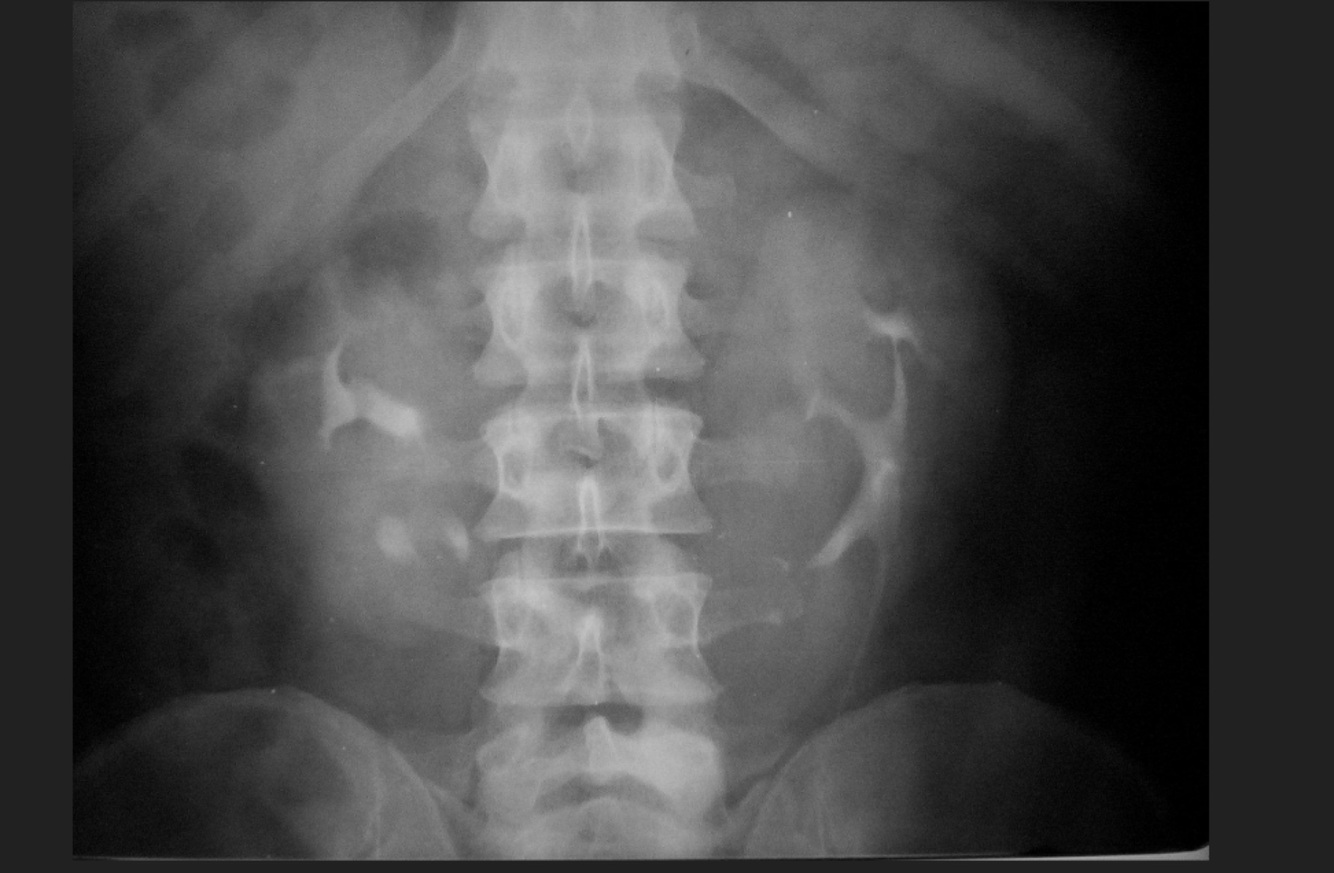

Femenino de 68 años. Dolor abdominal, distensión abdominal, imposibilidad para evacuación y canalización de gases 18 hrs

A

Oclusión intestinal